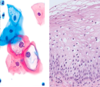

which histology is normal and which shows CIN

left - normal | right - CIN

what is cervical intraepithelial neoplasia

disorganised proliferation of abnormal cells in squamous epithelium (dysplasia) ``` lack of maturation variation in cell size and shape nuclear enlargement irregularity hyperchromasia cellular disarray ```

grades of CIN

1 - low grade dysplasia, HPV infection, will regress 2 - moderate, may regress esp in women <30y/o 3 - severe - unlikely to regress precursor of invasive cancer